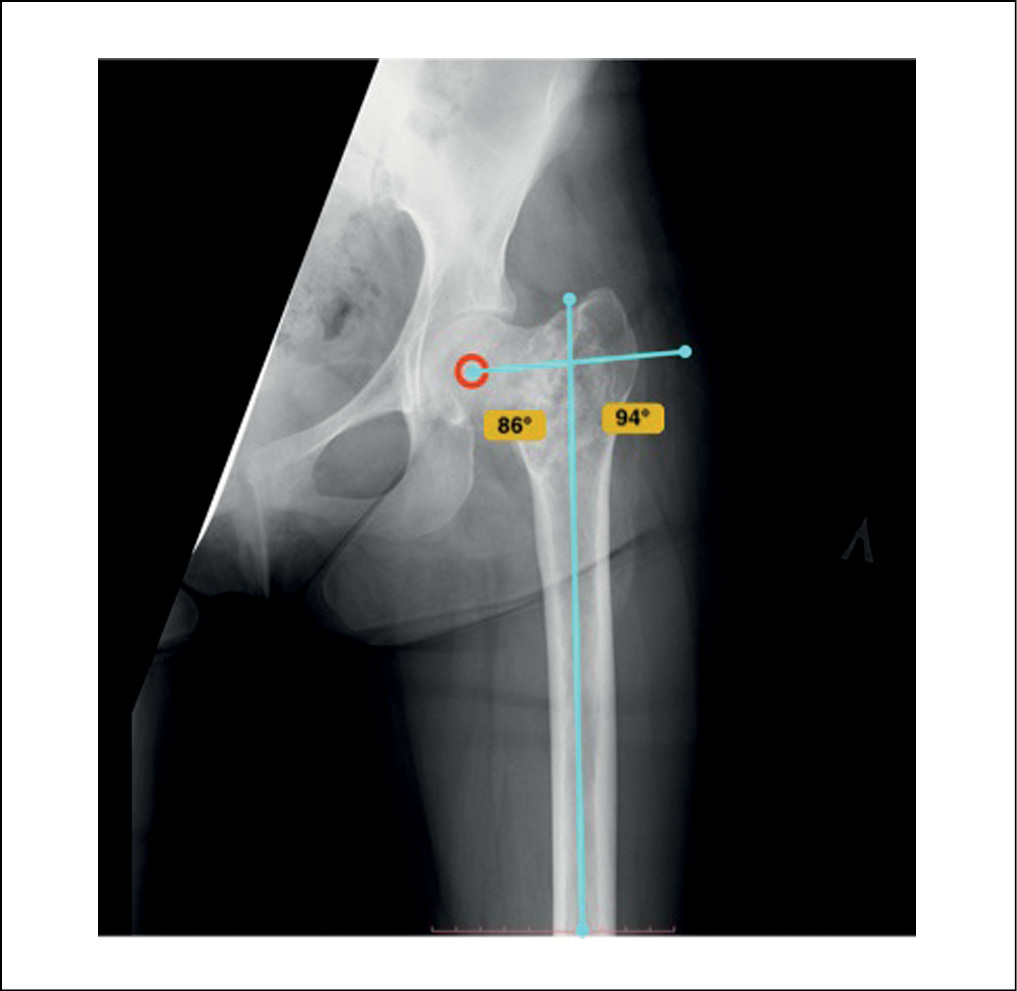

Армирование зоны расположения солитарной костной кисты не выполнялось ввиду анатомической особенности расположения патологического очага – очаг занимал обширную область шейки бедренной кости с распространением на базальную и вертельную зону до уровня малого вертела, а также затрагивал головку бедренной кости, что затрудняло установку винтов. По той же причине не выполнялась и коррекция сформированной варусной деформации проксимального отдела бедренной кости – шеечно-диафизарный угол (ШДУ) составлял 86°. Выполненная интраоперационно контрольная рентгенография левого тазобедренного сустава демонстрировала полное замещение полости костной кисты спонгиозным гомотрансплантатом (рисунок 2). Нижняя конечность была иммобилизирована в кокситной полимерной повязке на срок 8 недель.

Рисунок 2. Интраоперационная рентгенограмма левого тазобедренного сустава пациентки К., 2000 г.р., 2018 г. Отмечаются признаки наличия базального перелома бедренной кости в зоне солитарной костной кисты, смещения отломков с тенденцией к варусной деформации, ШДУ 86°. Полость кисты полностью заполнена гомотрансплантатом. / Figure 2. Intraoperative radiograph of the left hip joint of patient K., born in 2000, 2018. There are signs of a basal fracture of the femur in the area of the solitary bone cyst, displacement of fragments with a tendency to varus deformity, NSA 86°. The cyst cavity is completely filled with homograft.

При осмотре отмечались укорочение функциональной и анатомической длин левой нижней конечности на 2,0 см за счет бедренного сегмента, перекос таза влево, нарушение походки в виде прихрамывания на левую нижнюю конечность, ограничение активных и пассивных движений в левом тазобедренном суставе ввиду усиления болевого синдрома. На рентгенограмме области левого тазобедренного сустава была отмечена деформация проксимального отдела левой бедренной кости в виде консолидации отломков в положении варуса. При сравнительном анализе актуальных рентгенограмм и рентгенограмм, выполненных после операции по гомопластике костного дефекта, было отмечено отсутствие прогрессии варусной деформации проксимального отдела бедренной кости (ШДУ составлял 86° на обеих рентгенограммах). Также отмечались признаки полной реорганизации костного гомографта в зоне выполнения костной пластики, трабекулярная перестройка трансплантата, интеграция вновь сформированной костной ткани в общую архитектонику проксимального отдела бедренной кости. Кроме того, наблюдались признаки развития остеоартрита тазобедренного сустава на фоне варусной деформации проксимального отдела бедренной кости – снижение высоты суставной щели, признаки субхондрального остеосклероза головки бедренной кости, что соответствует 1 стадии заболевания по Келлгрену – Лоренсу (рисунок 4).

Рисунок 4. Рентгенограмма костей таза с захватом тазобедренных суставов пациентки К., 2000 г.р., 2021 г. Признаки ремоделирования зоны гомопластики с интеграцией сформированной кости в общую архитектонику проксимального отдела бедренной кости. Варусная деформация проксимального отдела бедренной кости с ШДУ 86°. Имеются признаки развития остеоартрита. / Figure 4. X-ray of the pelvic bones involving the hip joints of patient K., born in 2000, 2021. Signs of remodeling of the homoplasty zone with integration of the formed bone into the general architectonics of the proximal femur. Varus deformity of the proximal femur with NSA 86°. There are signs of osteoarthritis.